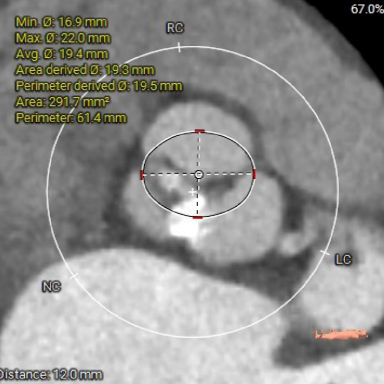

主动脉根部测量

瓣上结构测量

冠脉阻挡风险及钙化评估

1. Type 1 型二叶式主动脉瓣,瓣叶增厚伴中度钙化,L-N间钙化融合嵴,左室流出道呈敞口型;

2. 冠脉开口高度尚可,左右冠瓣叶冗长,切线位左右冠瓣叶长度>>冠脉开口到瓣叶根部附着缘距离;冠脉未见明显钙化斑块;

3. 三窦大小不一,瓦氏窦、窦管交界内径偏小,升主动脉轻度扩张;左室腔内径尚可,心室壁未见明显增厚;

4. 瓣环水平夹角51°,主动脉弓夹角偏锐利,弓距偏小;